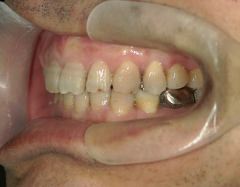

矯正歯科 治療前矯正歯科 治療前

矯正歯科 治療前 右上4番、左右下4番 計3本抜歯し、叢生を改善

no.22_8175_治療前_右.jpgno.22_8175_治療前_正面.jpgno.22_8175_治療前_左.jpg